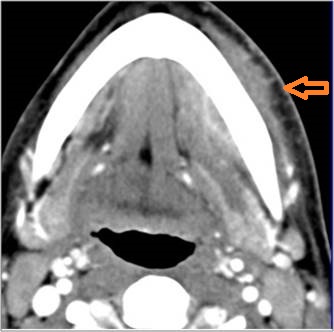

9 month old male presenting to the emergency room with poor feeding, fever, respiratory distress and possible retropharyngeal abscess or suppurative retropharyngeal adenitis.Exam

There is reactive retropharyngeal lymphadenopathy. |

There is suppurative retropharyngeal lymphadenopathy. |

Yes | NA |

If there is suppurative retropharyngeal adenopathy what is the maximum short axis dimension of the largest suppurative node. Measurement |

< 2cm | NA |

Pharyngitis with suppurative retropharyngeal adenitis.